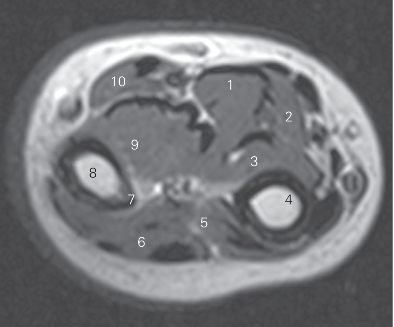

图4-36 经前臂中份的横断层MR T1加权图像

1 指浅屈肌 flexor digitorum superficialis 2 尺侧腕屈肌 flexor carpi ulnaris

3 指深屈肌 flexor digitorum profundus 4 尺骨 ulna

5 拇长展肌 abductor pollicis longus 6 指伸肌 extensor digitorum

7 骨间缘 interosseous border 8 桡骨 radius

9 拇长屈肌 abductor pollicis longus

10 桡侧腕屈肌 flexor carpi radialis